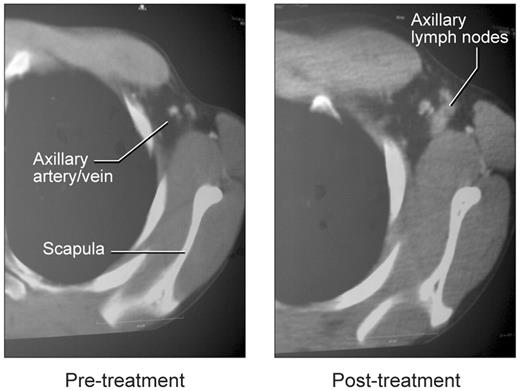

Effect of rCD40L treatment on lymph node architecture

To assess the effect of rCD40L on lymph node architecture, we compared the histology of pretreatment and posttreatment tissue in one patient and examined posttreatment tissue in the other 2 patients (Figure 4). Before treatment, all 3 patients lacked palpable axillary lymph nodes, and little or no lymphoid tissue could be identified based on CT examination (Figure 5). One patient had an inguinal lymph node biopsy before rCD40L therapy that revealed small, scattered aggregates of IgM+/IgD+ B cells. However, no germinal centers were seen, and the B cells were primarily located in abortive follicles that contained only scant follicular dendritic cells. This histologic finding is similar to that described in previous studies of lymph nodes of XHM patients.8,34

Appearance of lymph nodes in left axilla with rCD40L treatment. Before treatment, the arrow indicates the location of the axillary artery and vein on contrast-enhanced CT studies. The image on the right shows emergence of axillary nodes.

A substantially different picture was obtained at the end of rCD40L treatment when all 3 patients had easily visualized lymph nodes on CT examination (Figure 5). These were particularly evident in the axillary areas, possibly because the majority of rCD40L injections were given in the forearm. Biopsy and histologic examination of these nodes revealed prominent cortical primary follicles associated with a robust development of follicular dendritic cells (Figure 4). However, as in the pretreatment specimen, no germinal centers were observed, and only IgM+/IgD+ B cells were present. There was no change in spleen size or in the number of circulating lymphocytes. Consistent with the lack of induction of germinal center development, the patients did not mount IgG responses to challenge with KLH or bacteriophage φX-174. Serum immunoglobulin levels were unchanged, and IgE as well as IgA levels remained below the level of detection (supplemental Table 3). Immunophenotyping studies before and after rCD40L treatment, revealed that all peripheral blood B cells remained invariably naive with surface coexpression of IgD and IgM. The failure of memory B-cell differentiation in these patients was further confirmed in 2 of the 3 patients with analysis of somatic mutations in the heavy chain V3-23 Ig V gene35 (supplemental Table 4). These results show that although in vivo rCD40L treatment at the dose level used in this study induces development of primary follicles and a follicular dendritic cell network, it does not result in the development of germinal centers or a further differentiation of naive B cells in the periphery.